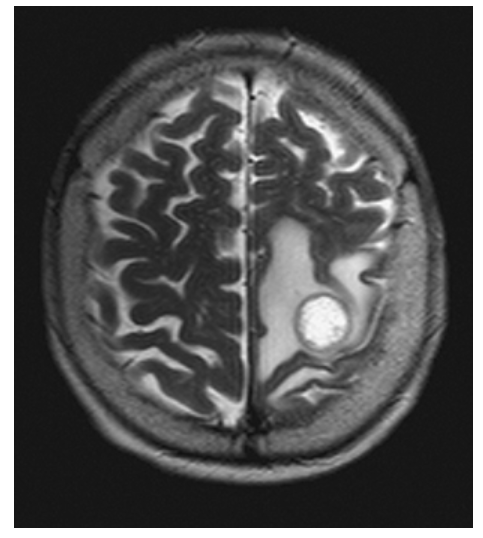

Brain Metastasis. Axial T2W image shows the left parietal mass with high central signal likely due to necrosis and high signal in the surrounding white matter due to vasogenic edema.